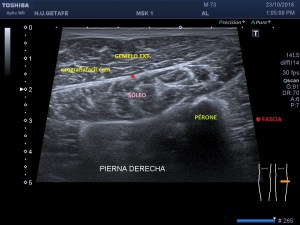

En la imagen 3 ves una imagen de un lipoma, mide 7 cms, la huella de la sonda mide 5cms, la «panoramic view» posee una regla centimetrada que sigue el contorno de la imagen, justo en la profundidad de la misma y lo marca la flecha amarilla. La profundidad la marca la flecha roja y la flecha blanca marca el rango centimetral de los 5cms, fíjate que la línea blanca es ligeramente mayor cada 5 cms. Sirve de referencia, como en la imagen 4 donde ves una colección en el glúteo de más de 10 cms.

Podemos medir valores superiores a los 15cms con alta calidad de imagen…podemos llegar a medir valores por encima de los 25 cms…es verdad que no todos los equipos tienen este ajuste ecográfico, es decir, es una aplicación y por tanto hay que pagarla.